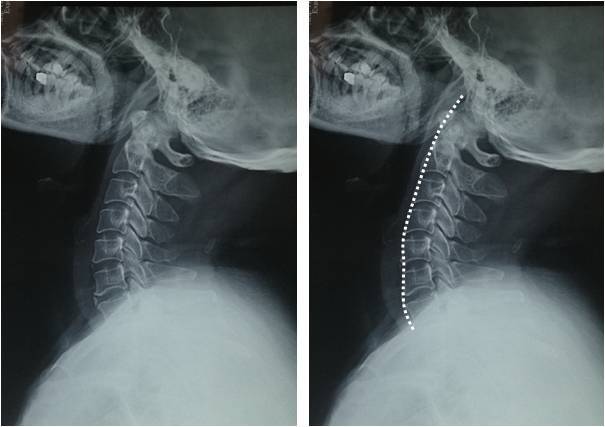

颈椎生理曲度变直一定是病吗 背后原因竟然这么多 健康资讯 娱乐新闻网

引起颈椎曲度改变的原因 一分钟自测颈椎曲度变直 肌肉 前凸 颈肩部 网易订阅

什么是颈椎 反弓 一把尺就能告诉你颈椎好不好